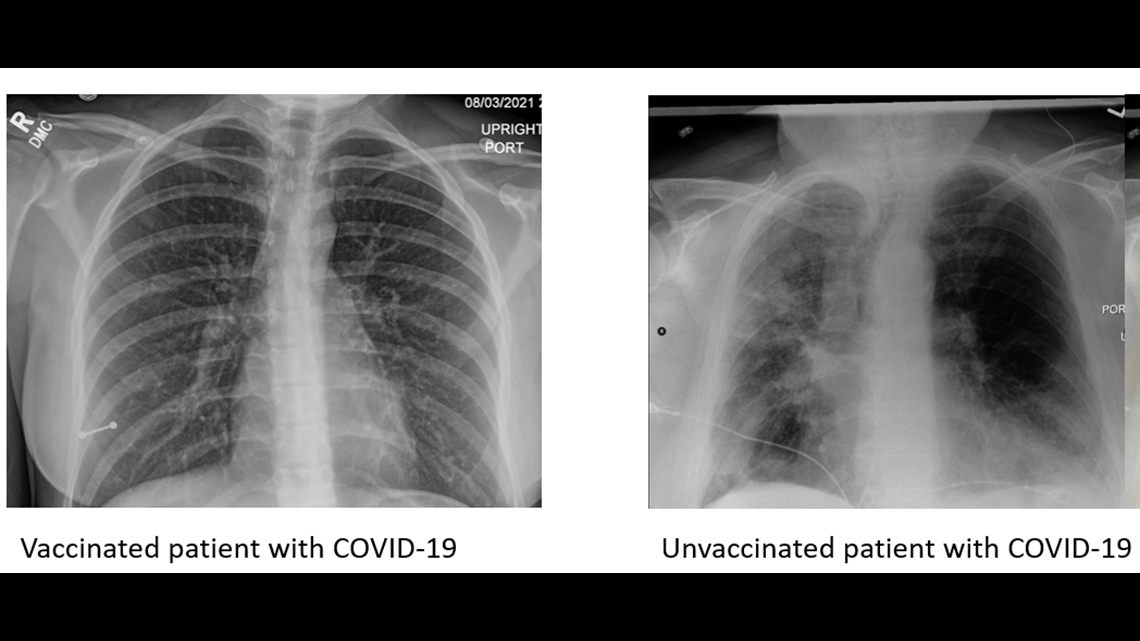

From www.cbs8.com

How do lung Xrays look between the vaccinated and unvaccinated? Can I Request A Lung X Ray There are often no signs or symptoms of lung cancer at an early stage. They can also show ongoing lung conditions, such. The targeted lung health check programme aims to. It uses a small amount. Your doctor has several ways to try to diagnose your heart disease. Can I Request A Lung X Ray.